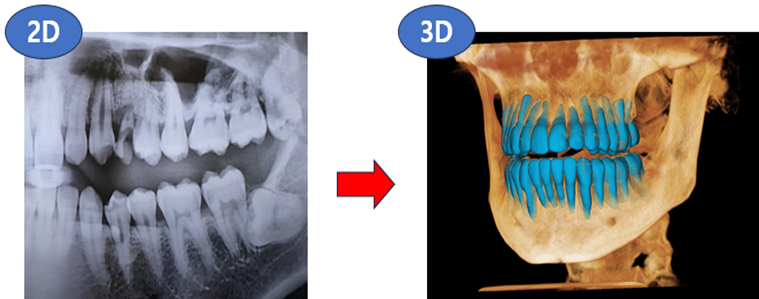

디지털진단장비는 X-ray로 구강을 진단하는 것을 의미해요. X-ray는 물체와 맞닿으면, 반사되기 때문에 치아, 잇몸속을 촬영할 수가 있죠. 이때, 일반 단면층을 촬영하면 2D X-ray라고 불러요. 반면, 여러 번 다양한 각도로 촬영을 한다면, 3D X-ray이이죠. 참고로, 3D X-ray를 흔히 알고 있는 CT(Computed Tomography)라고 부릅니다.

레이의 핵심은 '소프트웨어'에요. 사람을 사진(2D)으로 볼 때보다, 실제로(3D) 볼 때가 더 정확히 볼 수 있는 것 처럼 구강스캔을 통해 3차원 데이터로 표현하는 것이 레이의 경쟁력입니다. 레이의 H/W, S/W를 사용하는 의사입장에서도 빠르고 정확한 판단을 할 수 있기 때문에 치료 효율이 높아지는 효과가 생기겠죠.